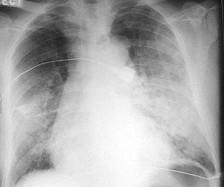

问题 男,67岁,近1个月出现活动后心悸、气短,双肺底可闻及湿性啰音,腹部检查肝脾肋下未触及,双下肢明显凹陷性水肿。胸部X线检查如图所示,超声心动图左室舒张末径61mm,左室射血分 数39%。 下列哪项治疗原则是错误的 ( )

选项 A、扩血管 B、ACEI C、利尿 D、β受体阻滞剂 E、强心

答案 D